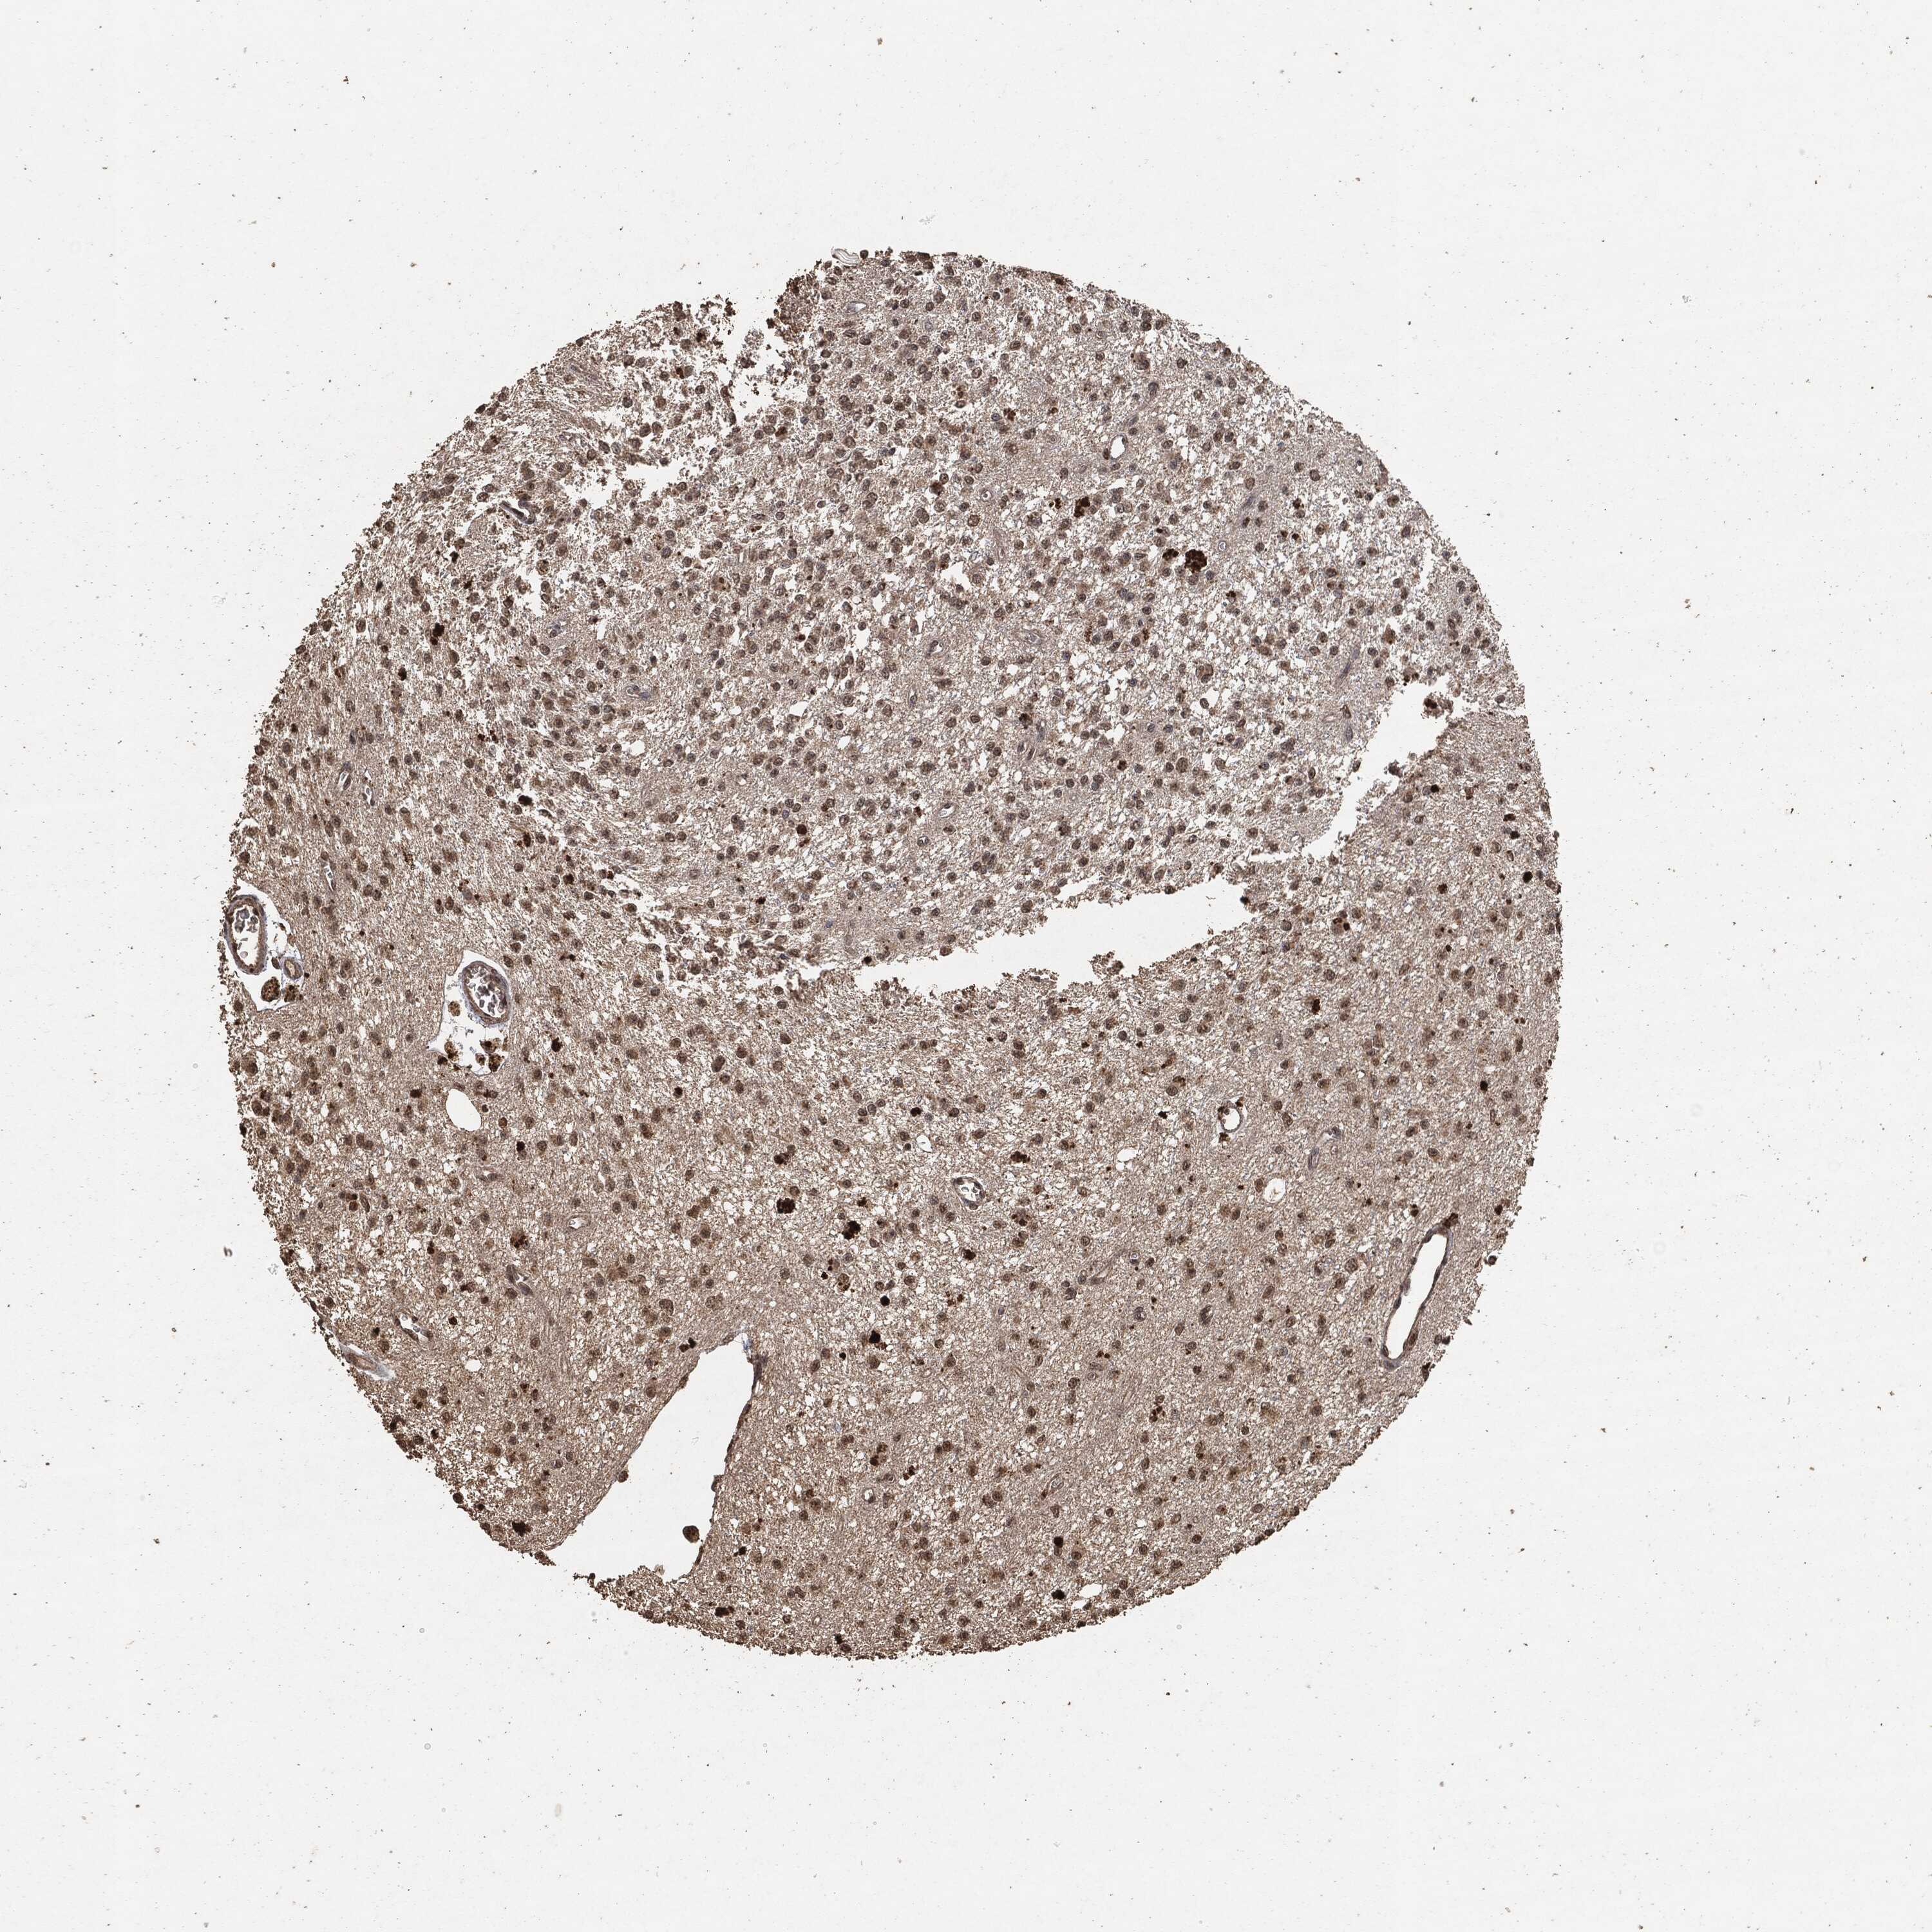

GLIOMA - Protein expressioni

A mouse-over function shows sample information and annotation data. Click on an image to view it in a full screen mode. Samples can be filtered based on level of antibody staining by selecting one or several of the following categories: high, medium, low and not detected. The assay and annotation is described here.

Note that samples used for immunohistochemistry by the Human Protein Atlas do not correspond to samples in the TCGA dataset.

Antibody stainingi

Antibody staining in the annotated cell types in the current human tissue is reported as not detected, low, medium, or high, based on conventional immunohistochemistry profiling in selected tissues. This score is based on the combination of the staining intensity and fraction of stained cells.

Each image is clickable and will lead to virtual microscopy that enables deeper exploration of all samples and also displays staining intensity scores, fraction scores and subcellular localization as well as patient and tissue information for each sample.

Glioma, malignant, High grade

Glioma, malignant, Low grade

Glioma, malignant, NOS